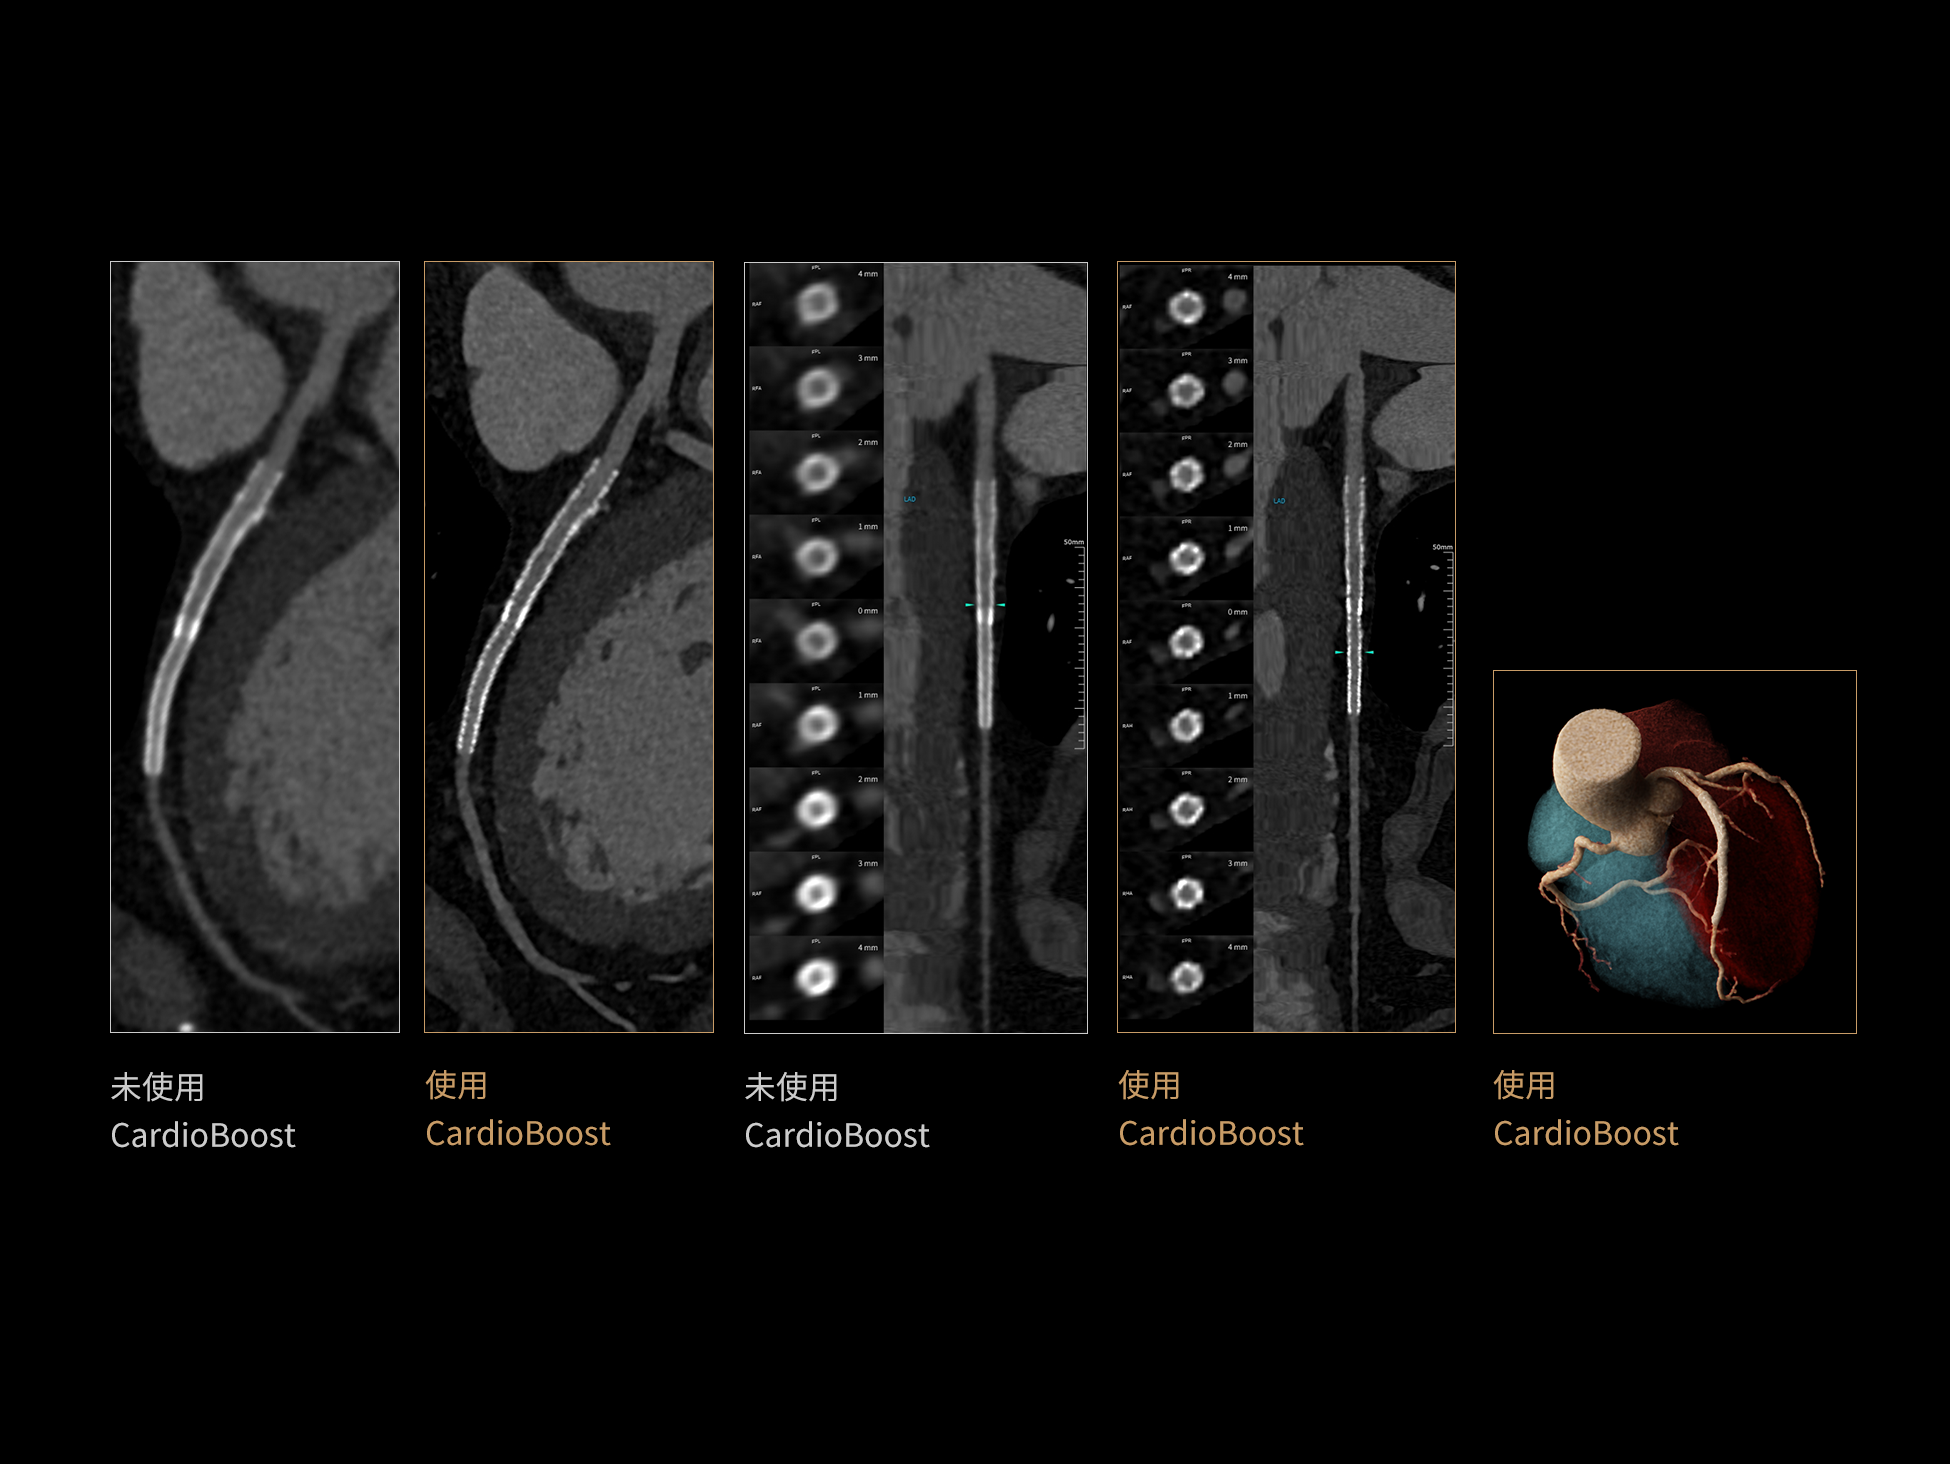

CardioBoost:专属网络设计,重塑心脏影像表现

目前心脏的 CT 检查还存在辐射剂量偏高、空间分辨率不足、 致密钙化伪影影响冠脉狭窄程度评估等方面的限 制[1][2]。CardioBoost 技术专为心脏 CT 高清成像而开发,通过 3D 神经网络的深度学习技术,利用先进的注意力机制在识别关键成像特征方面的出色表现,能够精确地聚焦于斑块、支架以及微小血管等关键细节,清晰展示这些结构与冠脉血管的边界,从而显著提高诊断的准确性,并提升医生的诊断信心。创新的 CardioBoost 心脏图像重建算法,不仅实现了图像清晰度的提升和伪影的去除,更能在减少辐射剂量的同时,保证心脏图像的高质量和图像纹理的自然。

采用 3D 神经网络的空间结构优势与精细的组织分类能力,CardioBoost 技术优化了组织对比,高清展示血管斑块,使斑块与血管边缘的轮廓清晰可辨,提升斑块诊断与评估的精确性。

借助 3D 神经网络设计、空间注意力机制聚焦与特征强化作用,CardioBoost技术提升图像的空间分辨率,实现冠脉支架的高清成像,对支架形态与管腔通畅度的评估更精准。

CardioBoost 整合先进的 3D 神经网络和空间注意力机制,大幅增强数据处理的速度与精确度。该技术能有效抑制由致密钙化引起的晕状伪影,清晰展现钙化斑块的原始结构和大小,对冠脉狭窄的评估更加精确可靠。